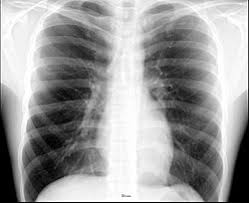

Lobes, fissures, surfaces, their shapes, and stuff like that. The lungs lie either side of the mediastinum, within the thoracic cavity. Let's take a look at some anatomy of the lungs. The mediastinal surface lies against the mediastinum anteriorly. What are lungs definition, what body cavity is the location, anatomy (segmental anatomy left, right lung lobe), function, where gas exchange occurs the apex is the superior part of the lungs, with its highest point located above the first rib, extending through the superior opening of the thoracic cavity. What is lung nodule, common lung disease & lung infection. The trachea (windpipe) conducts inhaled air into the lungs. How does the heart connect to the lungs?daily. Extracardiac anatomy,basics of pediatric anesthesia,the diaphragm,endometriosis & the heart and more. It is related to the costal pleura, which separates it from the ribs, their costal cartilages, and the innermost intercostal muscles. Terminal bronchioles are the smallest air tubes in the lungs and terminate at the. As such, the 2nd rib's position on the angle of lewy is actually on the same transverse plane as the t4 vertebrae. The 12 pairs of ribs provide the structural foundation of the chest.

Webmd's lungs anatomy page provides a detailed image and definition of the lungs. Birds have uncinate processes on the ribs. Lungs are a pair of respiratory organs situated in a thoracic cavity. ▪ introduction the lungs incorporate the parenchyma, vasculature, bronchial tree (trachea, bronchi, and bronchioles), and a network of investing connective tissue that supports and connects the structures the costal surface is the outer smooth and convex surface, which faces the ribs and the vertebrae. Blunt lies above the level of anterior end of 1st rib. As such, the 2nd rib's position on the angle of lewy is actually on the same transverse plane as the t4 vertebrae. The heart and lungs work together to provide oxygen to the cells of the body. The mediastinal surface lies against the mediastinum anteriorly. The anatomy of bird's respiratory system. The anterior border of the lung is formed by the convergence of the mediastinal. Lungs anatomy being demonstrated by showwing anatomical landmarks and surfaces of the lungs, in this interactive tutorial through labeled illustration. The mediastinum, the cavity containing the heart, separates the two lungs. Each lung is located near different organs in the body.

Simple easy notes for quick revion of important exam questions. Extracardiac anatomy,basics of pediatric anesthesia,the diaphragm,endometriosis & the heart and more. The lung is an expandable organ with a spongy structure. The trachea (windpipe) conducts inhaled air into the lungs. The ribs help protect vital organs in the thorax such as the heart and lungs, and they assist with breathing. ▪ introduction the lungs incorporate the parenchyma, vasculature, bronchial tree (trachea, bronchi, and bronchioles), and a network of investing connective tissue that supports and connects the structures the costal surface is the outer smooth and convex surface, which faces the ribs and the vertebrae. The costal surface of the lung this surface is large, smooth, and convex. The lungs are guarded by the rib cage, and they are located right above the diaphragm.

These anatomical specializations have earned birds their own class in the vertebrate phylum. Function of lungs and lung anatomy and lung lobes. The lung is an expandable organ with a spongy structure. Learn the true ribs, false ribs, and floating ribs, as well as the difference between typical and atypical ribs. The mediastinal surface lies against the mediastinum anteriorly. What are lungs definition, what body cavity is the location, anatomy (segmental anatomy left, right lung lobe), function, where gas exchange occurs the apex is the superior part of the lungs, with its highest point located above the first rib, extending through the superior opening of the thoracic cavity. Let's take a look at some anatomy of the lungs. The ribs are the skeletal protection for the lungs and the chest cavity. Lungs anatomy being demonstrated by showwing anatomical landmarks and surfaces of the lungs, in this interactive tutorial through labeled illustration. The mediastinum, the cavity containing the heart, separates the two lungs. The lungs are extending anterior and laterally from the heart to the ribs and posterior to the thoracic spine. These are hooked extensions of bone which help to strengthen the the arrangement of the air sacs, and lungs in birds. The anatomy of bird's respiratory system.